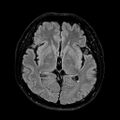

3. FLAIR((fluid attenuated inversion recovery;유체 감쇠 반전 회복)

1. 대표사진

2. 동영상-4

T2 FLAIR AX